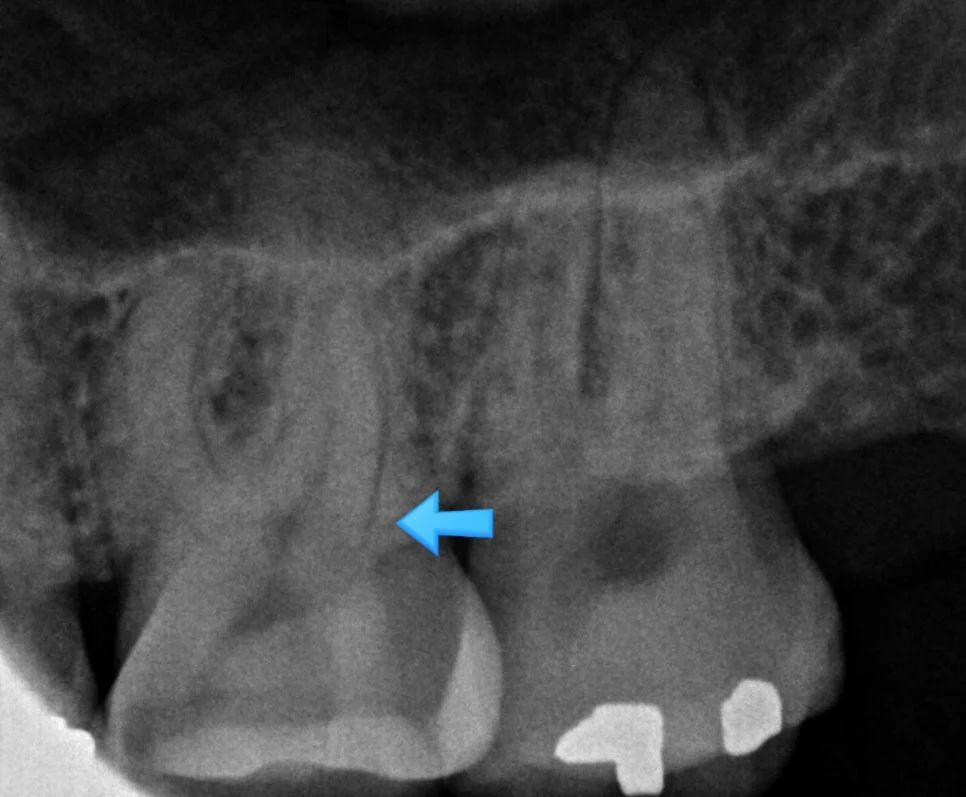

신경치료 진단 기준은? 치수염 증상과 통증, 비용까지 총정리

좋은 진료를 정직하게 | 선한 영향력으로 더 나은 가치를 신경치료 진단 기준은? 치수염 증상과 통증, 비용까지 총정리 강서구 마곡 서울쏙쏙치과 꿈꾸는 쏙쏙 치과의사 박상억입니다^^ 안녕하세요^^ 오늘은 신경치료에 대해 설명해 볼까 합니다. 우리나라에서는 신경치료라는 이름으로 불리지만 영어로는 Root Canal Treatment로, 치아의 뿌리를 치료한다는 근관치료라는 표현이 좀 더 적확한 표현입니다^^ 신경치료는 치아에서 감각을 느끼는 신경조직을 직접 다루는 … 더 읽기